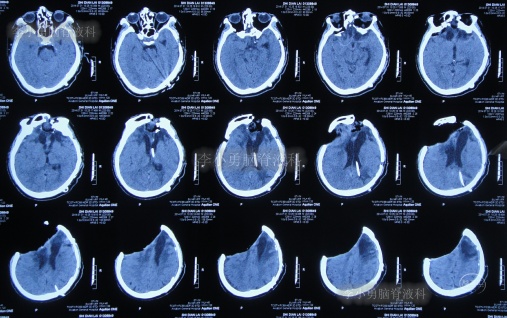

第3家医院出院后26天即2012年9月26日(开颅术后92天),因患者失语、嗜睡、吞咽障碍,第2次住入第3家医院,入院后2天即2012年9月28日,给予伤口及脑内脓肿清创缝合术+脑脊液漏修补术+右大腿取脂肪术,但术后2周即2012年10月12日,复查头颅CT提示脑积水(图-1)。

图-1:2012年10月12日头颅CT

2012年10月16日(第3家医院第2次住院20天),进行了脑室腹腔分流术(图-2)。

图-2:2012年10月16日头颅CT